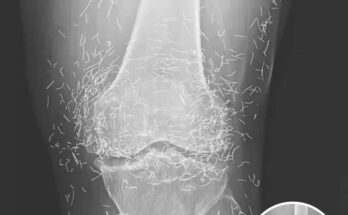

Doctors Stunned After Looking At This X-Ray Of Woman Suffering Joint Pain

When doctors reviewed a routine X-ray of a 65-year-old woman suffering from chronic joint pain, they expected to find the usual signs of osteoarthritis—bone erosion, cartilage loss, maybe some swelling. …